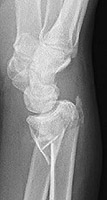

Also called a reverse Colles fracture, the Smith fracture is a transverse fracture of the distal radial metaphysis with palmar (as opposed to dorsal) displacement of the distal fracture fragment. If the fracture is intraarticular, it is called a reverse Barton fracture. This fracture results from a backward fall onto the outstretched hand.

- Click on the image for a larger versionALateral radiograph of the wrist. This demonstrates a distal radial fracture. There is palmar displacement of the distal fracture fragment.